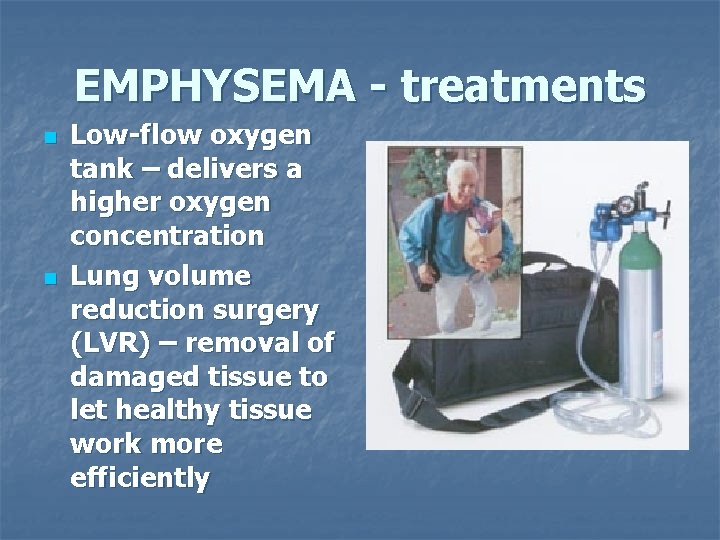

EMPHYSEMA - treatments n n Low-flow oxygen tank – delivers a higher oxygen concentration Lung volume reduction surgery (LVR) – removal of damaged tissue to let healthy tissue work more efficiently